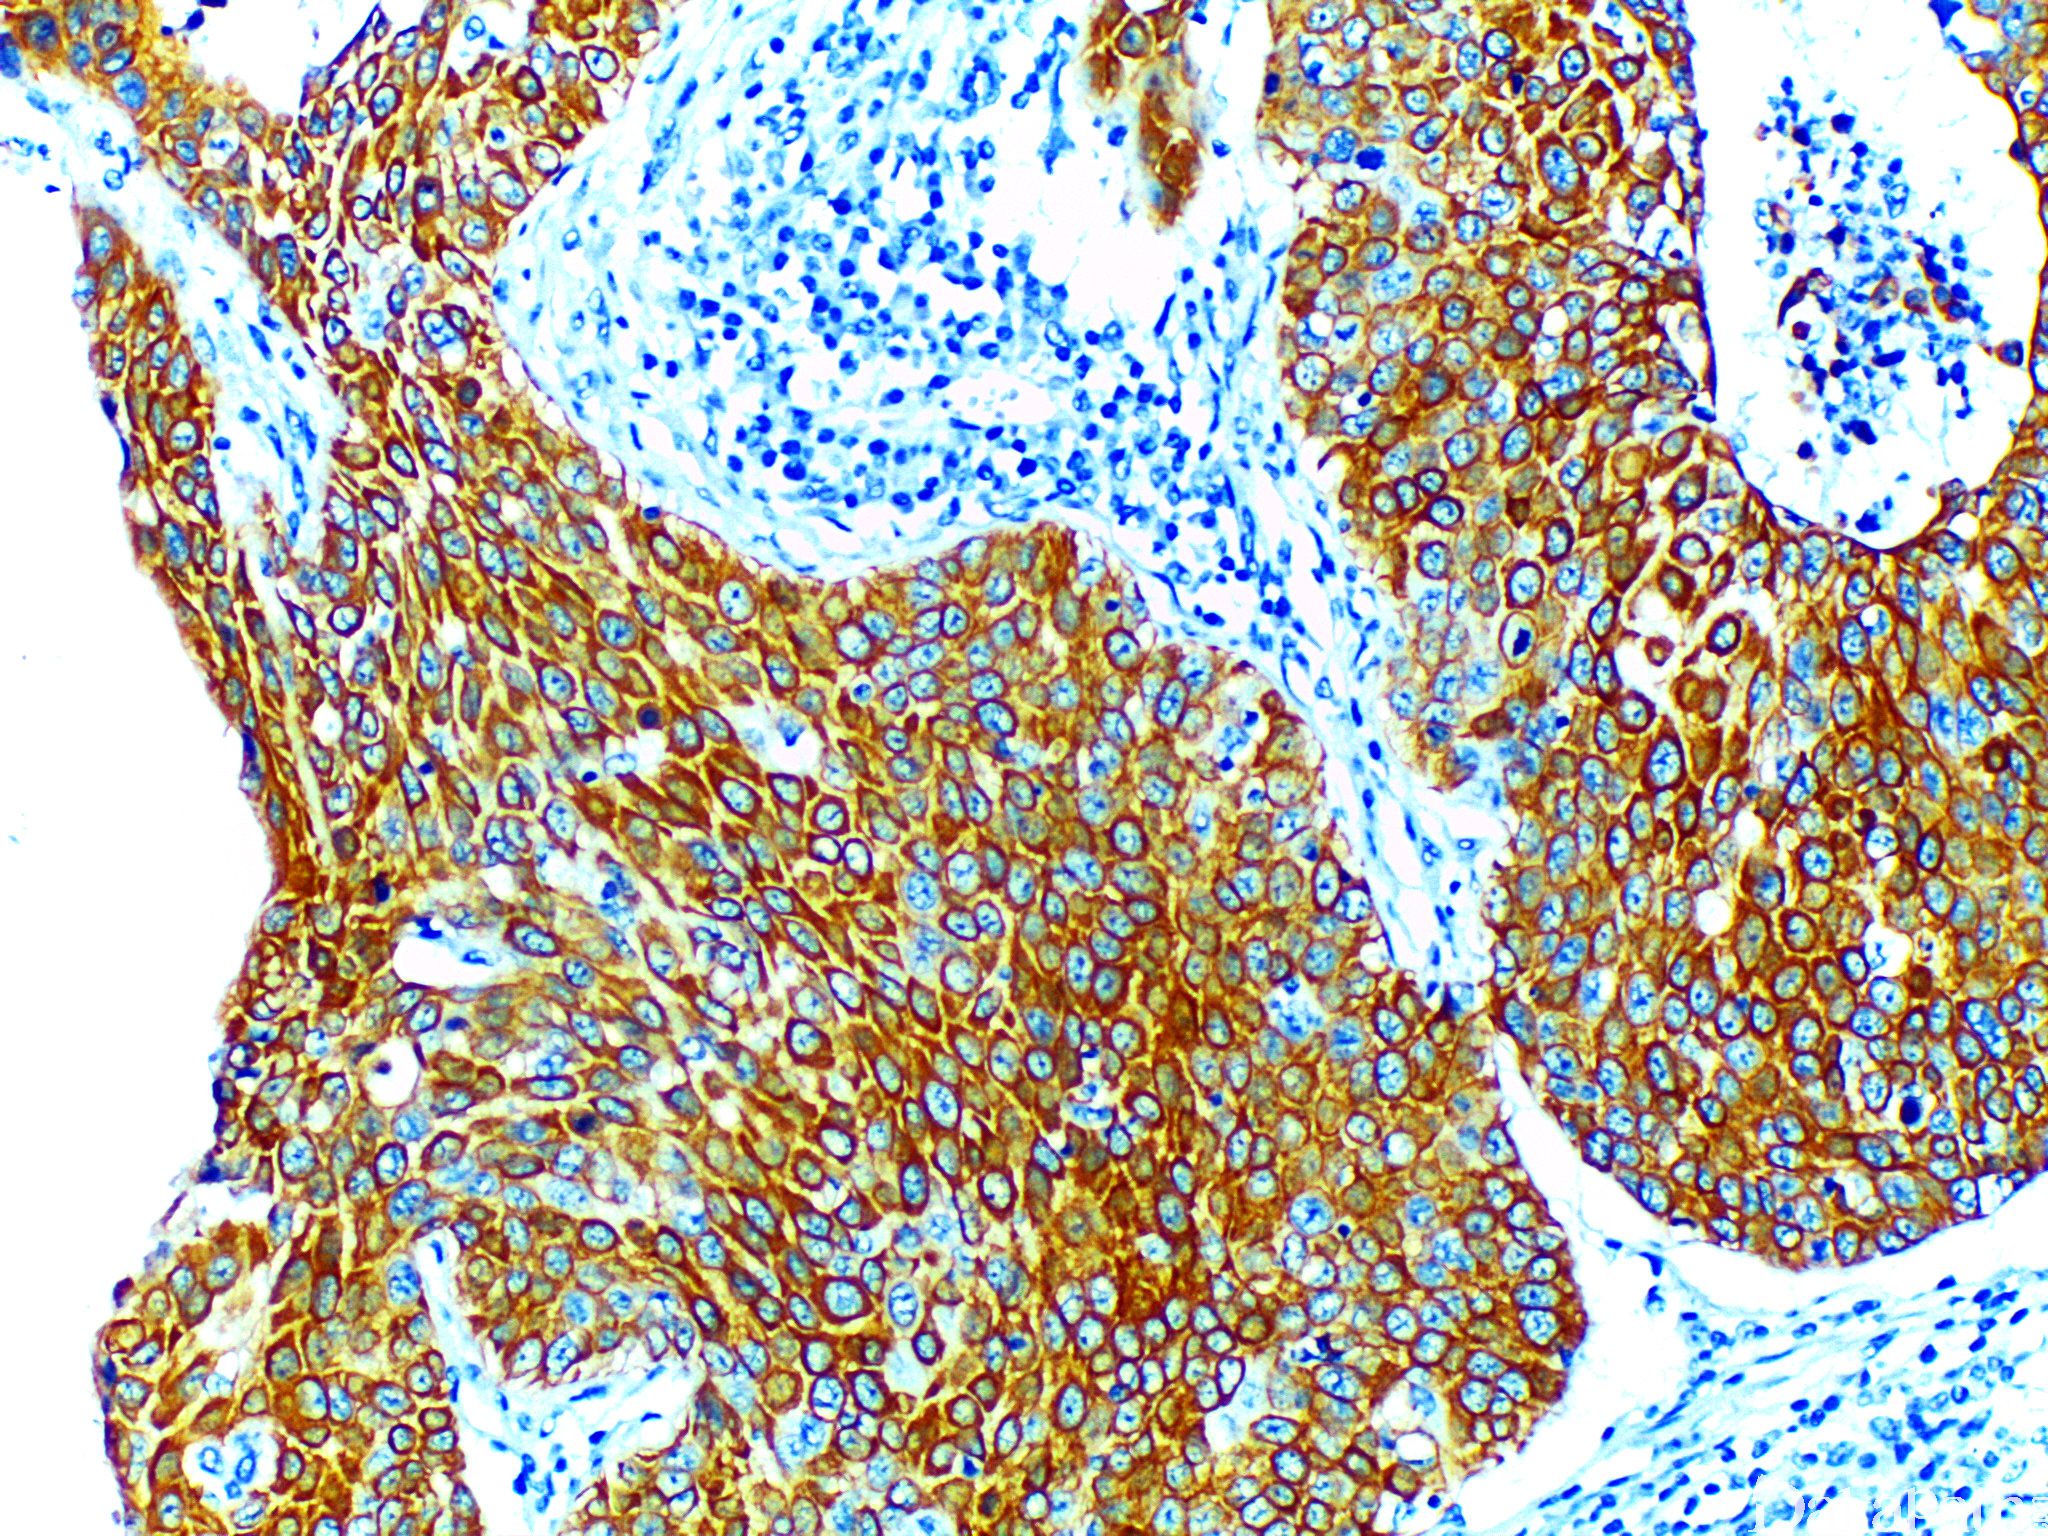

CK5

II 型细胞角蛋白,分子量为 58kD,表达于鳞状上皮及腺体的基底细胞。

信号定位: 胞质

通常阳性(<95%,≥75%的病例阳性): 上皮样间皮瘤、间皮瘤,NOS、乳腺化生性癌、甲状腺间变性癌、肺鳞状细胞癌、脊索瘤、乳腺囊性高分泌型导管内乳头状癌、乳腺髓样癌